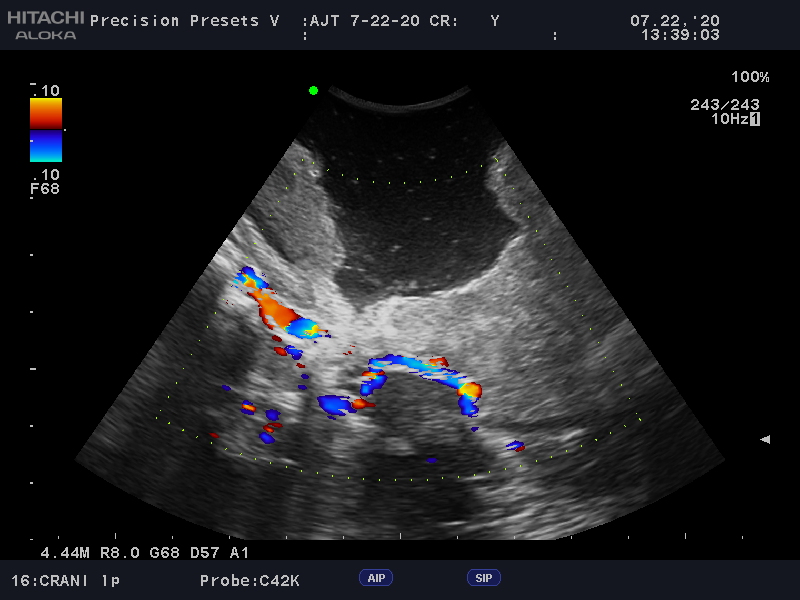

Learn moreArietta Precision

Fujifilm Healthcare’s ARIETTA Precision features state-of-the-art digital architecture and advanced imaging technologies to redefine the capabilities of surgical ultrasound.

Learn moreArietta Precision

Fujifilm Healthcare’s ARIETTA Precision features state-of-the-art digital architecture and advanced imaging technologies to redefine the capabilities of surgical ultrasound.